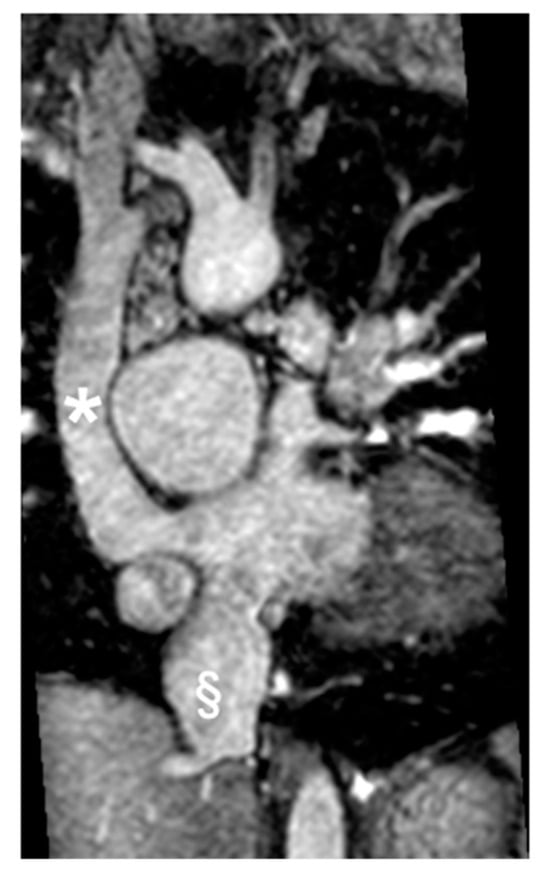

- Leo, I.; Sabatino, J.; Avesani, M.; Moscatelli, S.; Bianco, F.; Borrelli, N.; De Sarro, R.; Leonardi, B.; Calcaterra, G.; Surkova, E.; et al. Non-Invasive Imaging Assessment in Patients with Aortic Coarctation: A Contemporary Review. J. Clin. Med. 2024, 13, 28. [Google Scholar] [CrossRef]